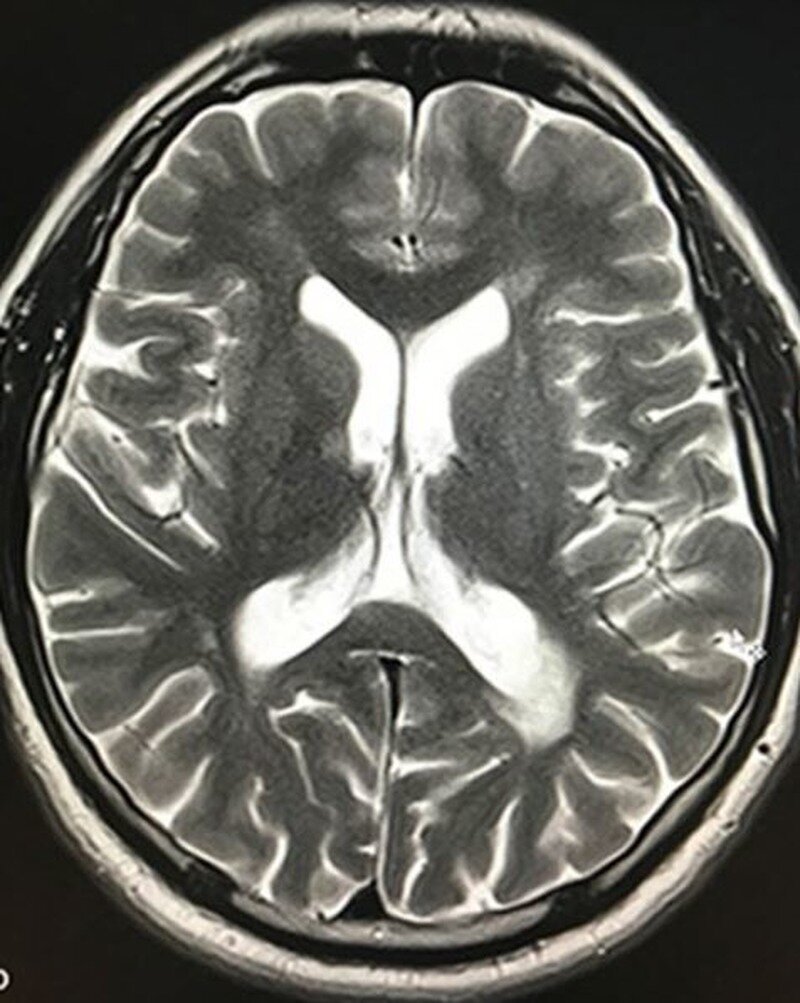

МРТ головного мозга